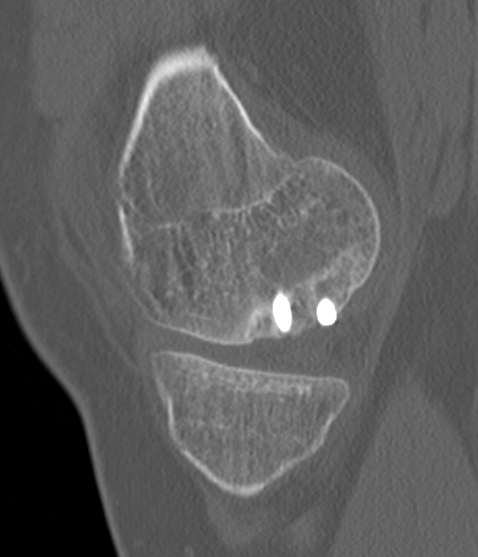

MFC unstable OCD

LFC unstable OCD